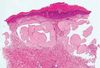

60 year old male w/ dorsal hand biopsy

Colloid milium

- Dermal “goo”

- Amorphous pink material with cracking in b/w

- Hands and face

- Older people